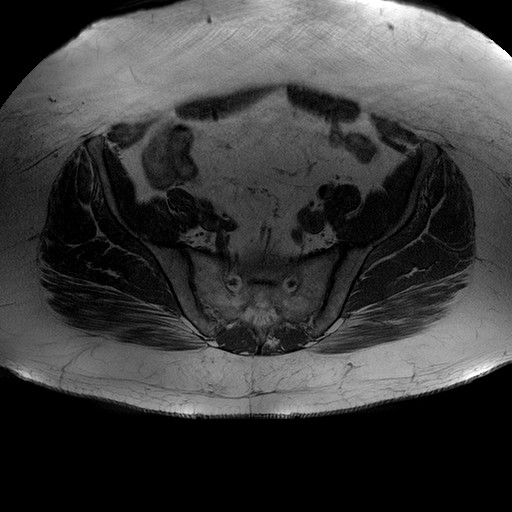

Esami: RMN BACINO

T1W_TSE

Evidenti e simmetriche alterazioni osteofitosiche in regione coxo femorale con riduzione delle rime articolari. Degenerazione completa del cercine glenoideo. Non attuali segni di versamento articolare. Non segni di edema osseo che escludono attuale algodistrofia od osteonecrosi. Lieve e simmetrica riduzione del trofismo della muscolatura glutea.